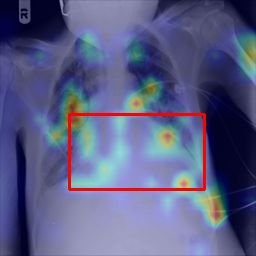

Deployments of artificial intelligence in medical diagnostics mandate not just accuracy and efficacy but also trust, emphasizing the need for explainability in machine decisions. The recent trend in automated medical image diagnostics leans towards the deployment of Transformer-based architectures, credited to their impressive capabilities. Since the self-attention feature of transformers contributes towards identifying crucial regions during the classification process, they enhance the trustability of the methods. However, the complex intricacies of these attention mechanisms may fall short of effectively pinpointing the regions of interest directly influencing AI decisions. Our research endeavors to innovate a unique attention block that underscores the correlation between 'regions' rather than 'pixels'. To address this challenge, we introduce an innovative system grounded in prototype learning, featuring an advanced self-attention mechanism that goes beyond conventional ad-hoc visual explanation techniques by offering comprehensible visual insights. A combined quantitative and qualitative methodological approach was used to demonstrate the effectiveness of the proposed method on the large-scale NIH chest X-ray dataset. Experimental results showed that our proposed method offers a promising direction for explainability, which can lead to the development of more trustable systems, which can facilitate easier and rapid adoption of such technology into routine clinics. The code is available at www.github.com/NUBagcilab/r2r_proto.